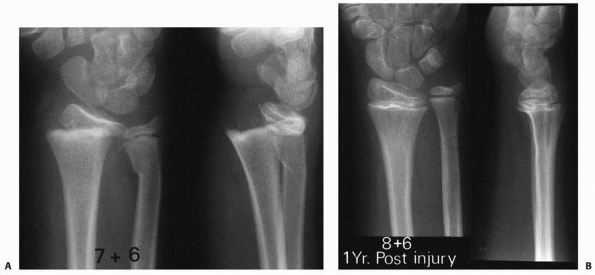

| Figure 5-18 Potential mechanism of physeal arrest development after Salter-Harris type II fracture of the distal radius. A. Dorsally displaced type II fracture of the distal radius. Note the evidence of impaction of the epiphyseal fragment (with the physis) by the dorsal margin of the proximal fragment metaphysis. B. One year later, there is radiographic evidence of physeal arrest formation in the distal radial physis. |